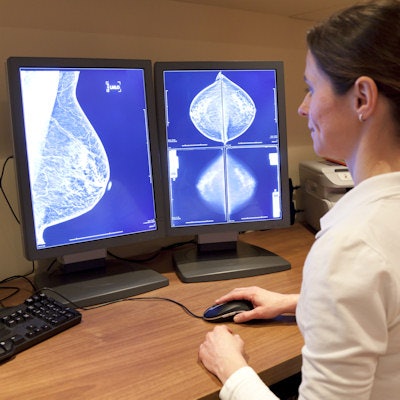

Artificial intelligence (AI) could effectively reduce the workload involved in reading mammography screening exams by eliminating studies most likely to be normal from the radiologist's worklist, according to a presentation delivered at ECR 2019 in Vienna.

The results suggest that it's feasible to use AI to cut radiologists' mammography reading workload, said presenter Dr. Kristina Lång, PhD, of Lund University in Sweden.

The mammograms were analyzed with deep learning-based computer-aided detection (CAD) software (Transpara, ScreenPoint Medical), which categorizes them with a risk score of 1 to 10, with 10 being the highest risk of malignancy, Lång said. The group then evaluated the performance of the AI algorithm in screening whether normal exams could be excluded, and what types of cancers the AI system missed. A team of three radiologists assessed the visibility of the cancers that AI missed.